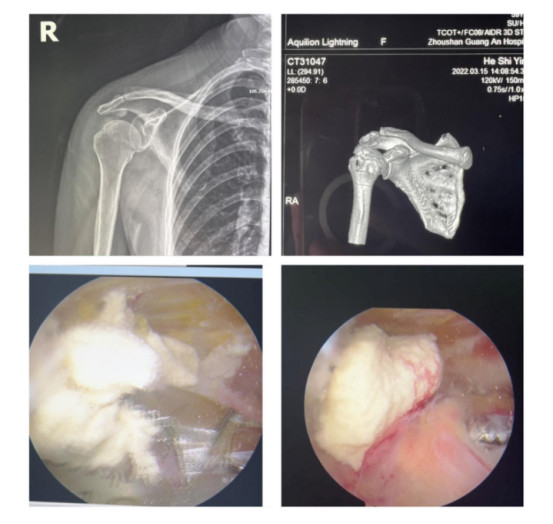

賀大媽慕名來(lái)廣安醫(yī)院找羅軍主任就診,面對(duì)羅醫(yī)生,賀大媽哭訴:“羅醫(yī)生,我真想剁下自己的這只胳膊。”羅軍主任根據(jù)患者的癥狀拍片,診斷為岡上肌鈣化性肌腱炎,隨后,羅醫(yī)生為李大媽進(jìn)行了肩關(guān)節(jié)鏡微創(chuàng)手術(shù),竟從她的右肩“擠”出“牙膏”。

鈣化性肌腱炎是一種自限性疾病,就是疾病發(fā)生發(fā)展到一定程度后,經(jīng)長(zhǎng)期機(jī)體調(diào)節(jié)能夠控制病情發(fā)展并逐漸恢復(fù)痊愈。它分為四個(gè)階段:鈣化前期、鈣化形成期、鈣化吸收期、鈣化后期,往往在“鈣鹽斑塊”吸收時(shí),疼痛最劇烈,賀大媽就正處于“吸收期”。

是不是只要病人撐得住,讓鈣鹽吸收就沒(méi)事了?羅軍主任表示,經(jīng)保守治療無(wú)法緩解或病程長(zhǎng)的患者,應(yīng)盡早采取手術(shù)治療。而且,部分患者鈣鹽無(wú)法完全吸收,拖下去只會(huì)使病情惡化,造成肩膀肩袖肌腱的損傷。

羅軍主任表示,很多人會(huì)把肩痛都?xì)w因于肩周炎,這是一個(gè)很大的誤區(qū)。其實(shí),肩痛人群中只有15%左右是肩周炎,大部分肩膀疼痛由于肩袖損傷、肩峰撞擊征、鈣化性肌腱炎。而大多數(shù)人也因此認(rèn)為忍一忍就會(huì)自愈,常常延誤治療,關(guān)節(jié)鏡微創(chuàng)治療鈣化性肌腱炎,可以快速緩解疼痛,同時(shí)可以修復(fù)肩袖損傷,清理肩膀骨刺。